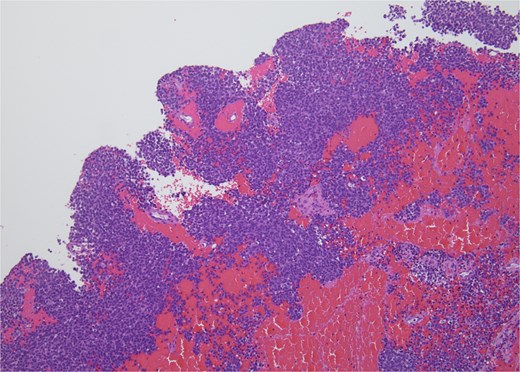

Molecular staining further supported an ES diagnosis (Fig. 4). Immunohistochemical staining with NKX2.2, which is highly specific for ES, demonstrated positive nuclear staining of neoplastic cells. Furthermore, molecular testing confirmed the presence of an EWS fusion.

CD99, 20×. Immunohistochemical stain with CD99 demonstrates diffusely positive membranous staining of neoplastic cells.